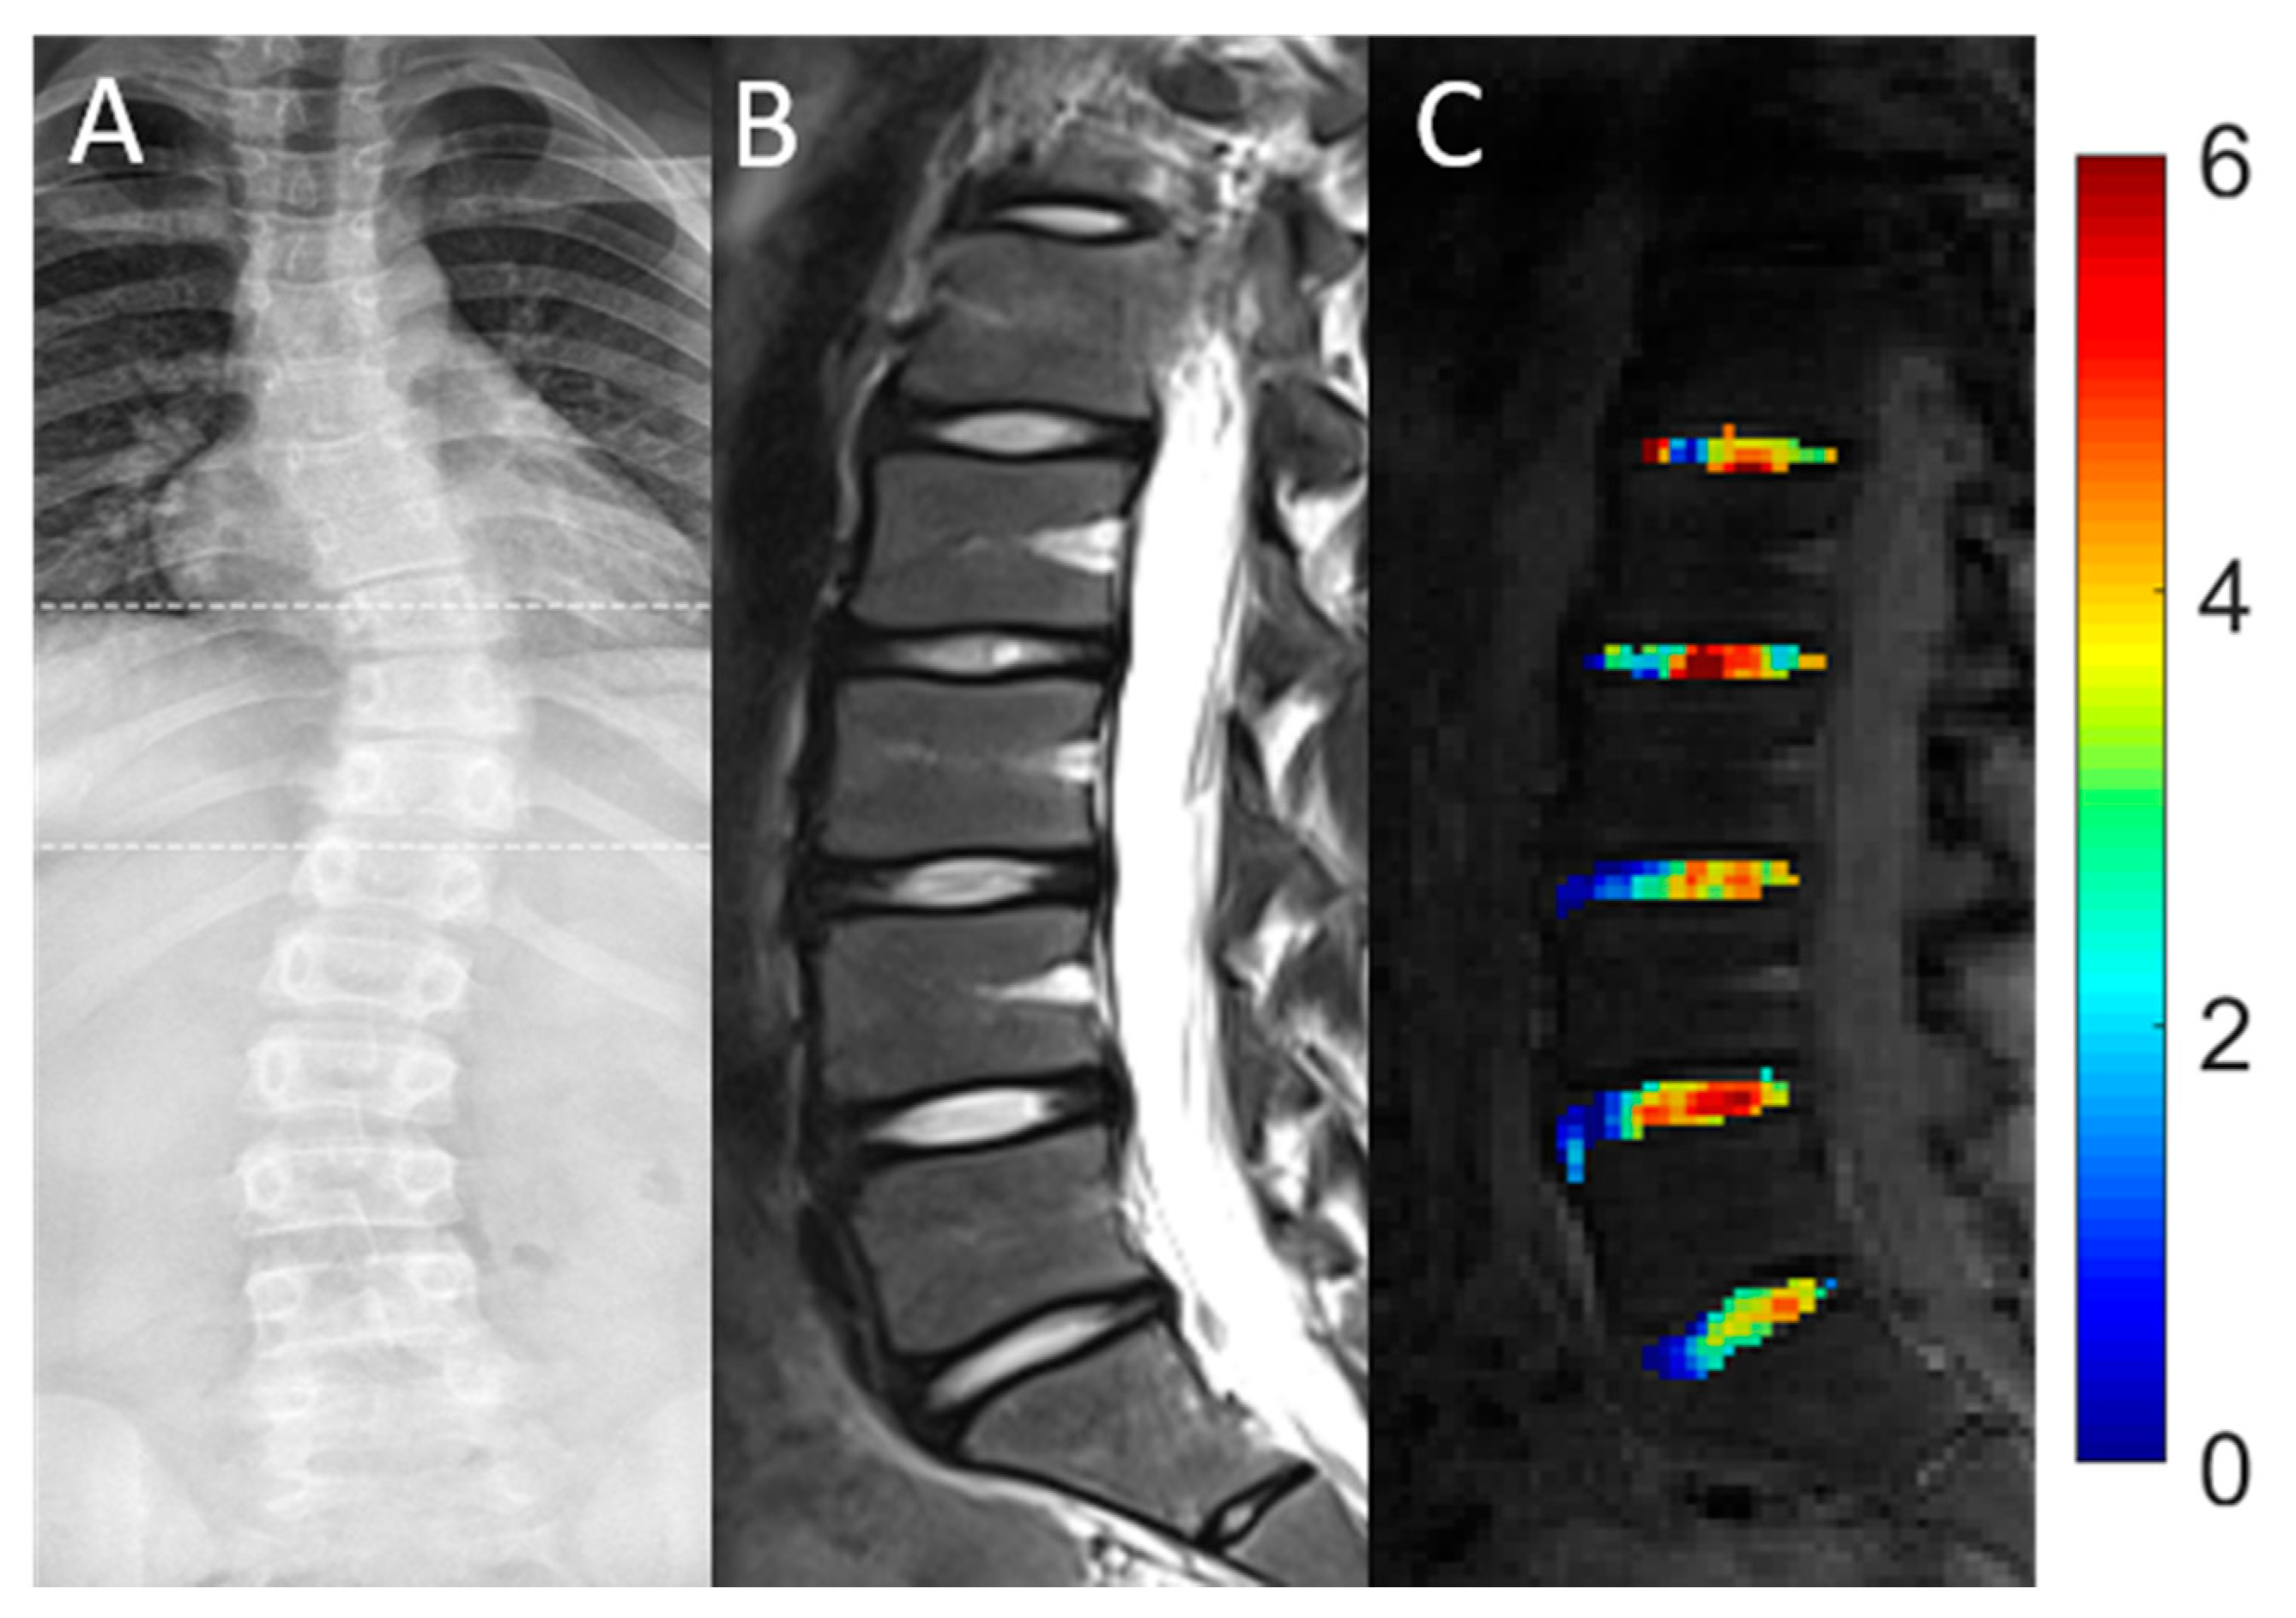

1. Introduction

2. Materials and Methods